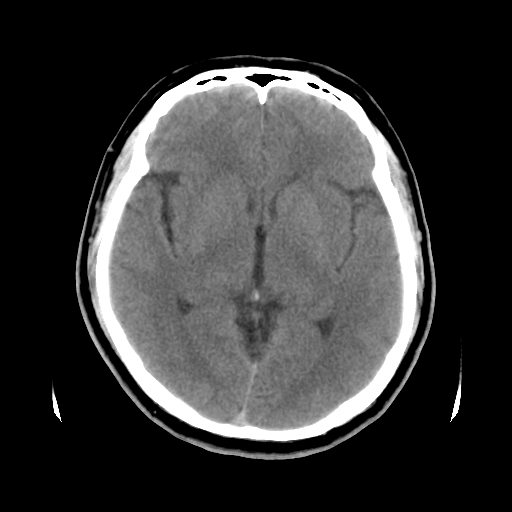

标题: CT15194:男,53岁,头痛、恶心三天。 [打印本页]

男,53岁,头痛、恶心三天。

筛窦囊肿、颅内未见明确异常

考虑筛窦内粘液囊肿可能性大。

支持左侧筛窦后组粘液囊肿。